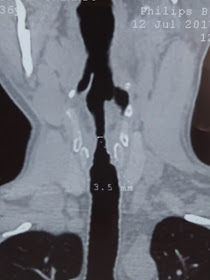

Varón de 37 años con granulomatosis de Wegener y

mala adherencia al tratamiento que consulta por disnea al esfuerzo.

En la reconstrucción coronal y sagital de la vía aérea se observa estenosis por debajo del nivel de la glotis el cual es predominantemente en el sentido transversal sobre el anteroposterior.